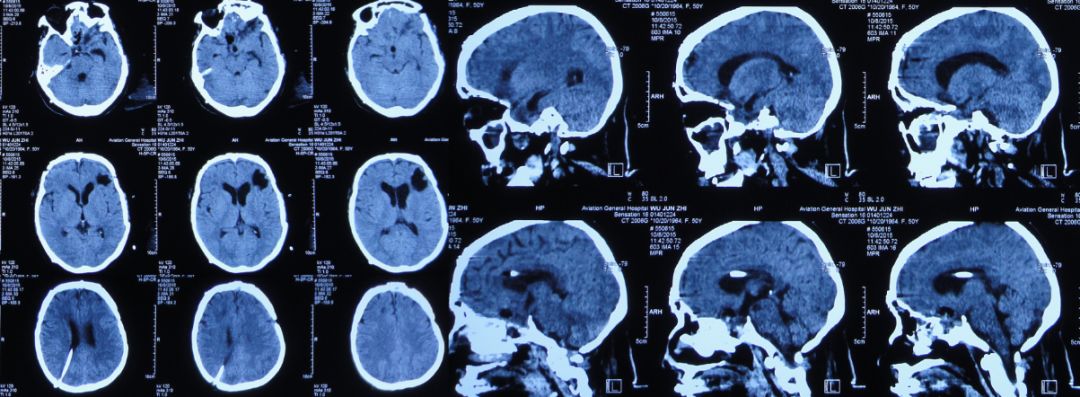

患者女,50岁,安徽省淮北市人。2014年12月14日,患者因高处坠落伤(2米左右)伤及头胸部及四肢,致昏迷,左耳、左鼻流血性液体,急诊前往安徽省淮南市潘集区某医院急查头CT显示左额叶脑挫伤、左侧颞骨凹陷性骨折、脑肿胀、颅内积气(图1);眼眶CT显示双侧眼眶内侧壁骨折(图2);胸部CT显示左侧肋骨骨折伴肺挫伤;右上肢X片显示右桡骨远端粉碎性骨折;左肩部X片显示左侧锁骨骨折。立即给予住院,保守治疗。

图1:2014年12月14日头CT:左额叶脑挫伤、左侧颞骨凹陷性骨折、脑肿胀、颅内积气